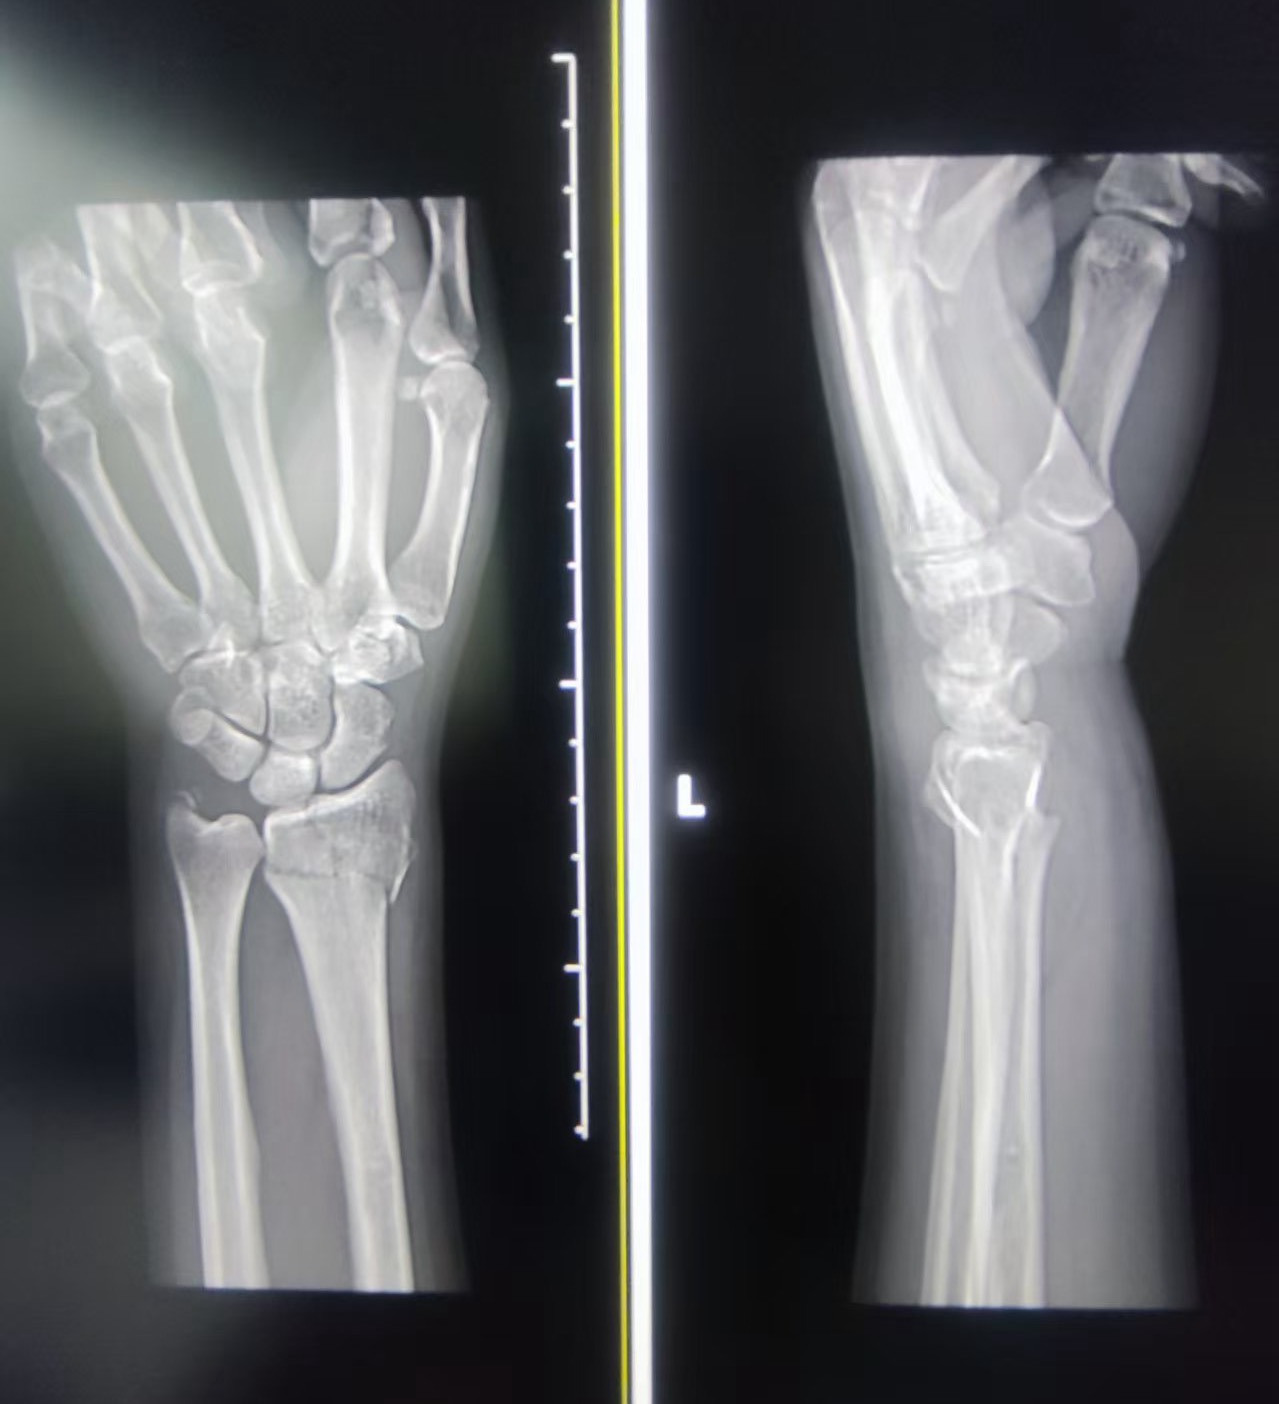

疼痛难忍,王女士赶到了浙江省中山医院骨伤科就诊,接诊的副主任医师蔡军辉立即为她安排了相关检查,X光片显示,王女士的右侧桡骨远端骨折,蔡军辉应用手法复位技术为其治疗。

骨折影像(医院供图)

蔡军辉表示,对于桡骨远端骨折,大部分情况可以通过手法复位、石膏或小夹板外固定等保守治疗获得良好恢复。如果骨折移位明显、不稳定或涉及关节面,可能需要进行手术治疗。